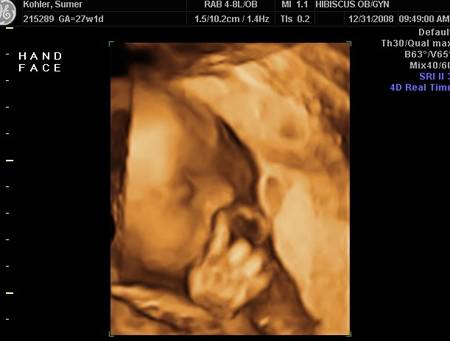

Nu mereu reușești să surprinzi atât de bine anumite imagini de ecograf. Tocmai de aceea, imaginile prezentate sunt foarte RARE!

De-a lungul timpului au fost surprinse mai multe imagini de ecograf cu adevărat uluitoare!

Iată mai jos 10 imagini de ecograf unice!